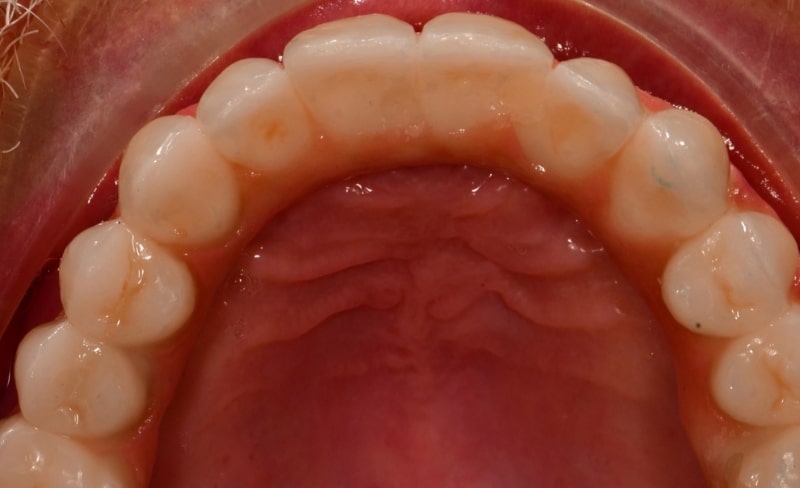

Upper and lower all-on-4 dental implants to restore function and aesthetics.